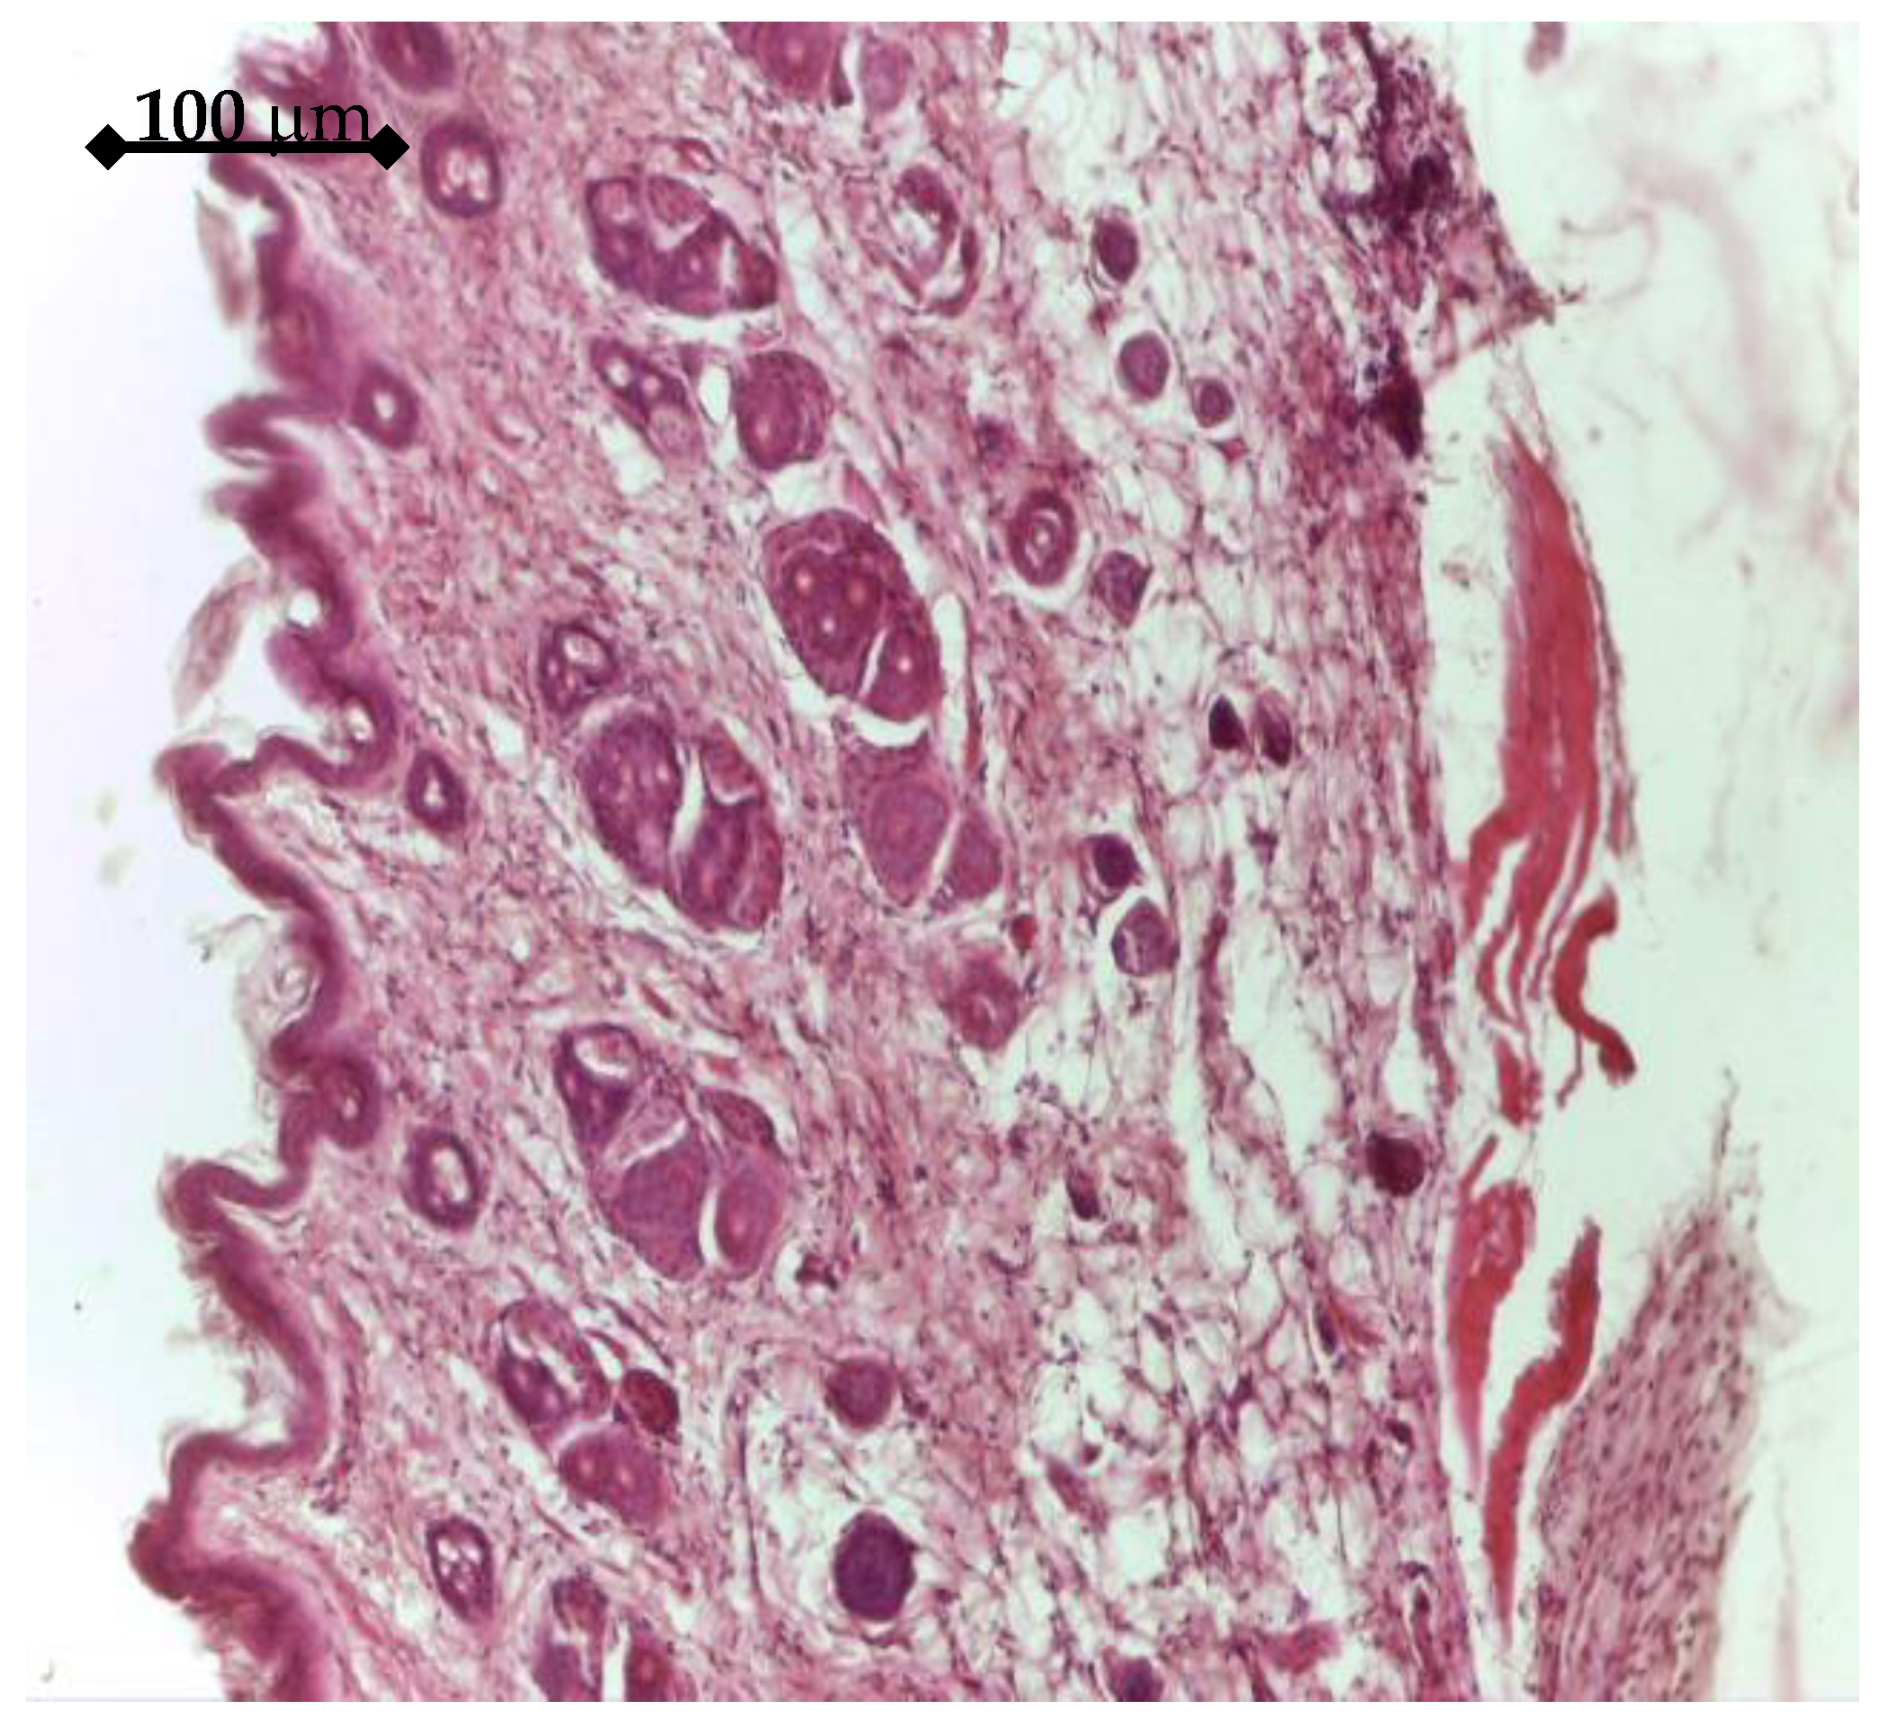

BMP2 releasing samples had a different histologic effect. After 14 days, an accentuated fibrosis process could be seen in the dermis, both at the superficial level, where an increase in the number of collagen fibers could be observed, and at the deep level, Figure 16. In the vicinity of the implant, mesenchymal tissue, with cellular star-like elements can be seen.

Figure 16. Tissue around BMP2 Ti sample (14 days), Hematoxylin eosin staining: Tegument with numerous bundles of collagen fibers, both in the superficial dermis and in the deep dermis, 20×.